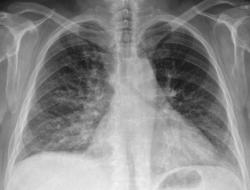

Добрый день коллеги! Сегодня проглядывал снимочки легких, по просьбе своей коллеги, с целью исключения метастазов и увидел  представленную картину. Пациентка 50 лет, лежит  в стационаре с диагнозом: Злокачественное новообразование яичника? Мts в надключичные лимфатические узлы. Мысли сразу про лимфогенные метастазы,  поглядел сразу в архиве ФЛГ от 11.08.09г. два первых снимка, два последних сегоднишним днем. Ваше мнение?

Два последних снимочка это сегоднишние цыфровые рентгенограммы, КТ-у нас пока вышло из строя. По УЗИ находят образование в почке и яичнике.